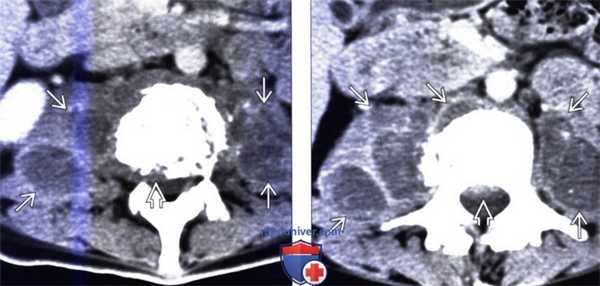

(Слева) Аксиальный КТ-срез с КУ: деструкция позвонка с формированием двусторонних абсцессов поясничных мышц. Видны признаки эпидурального распространения процесса со стенозированием спинномозгового канала.

(Справа) Аксиальный КТ-срез с КУ: деструкция позвонка с формированием двусторонних абсцессов поясничных мышц. Видны признаки эпидурального распространения процесса со стенозированием спинномозгового канала. В острую фазу процесса на диффузионно-взвешенных МР-И будет отмечаться гиперинтенсивность сигнала тел позвонков, замыкательных пластинок и межпозвонковых дисков, тогда как при хроническом процессе будет гипоинтенсивность сигнала.